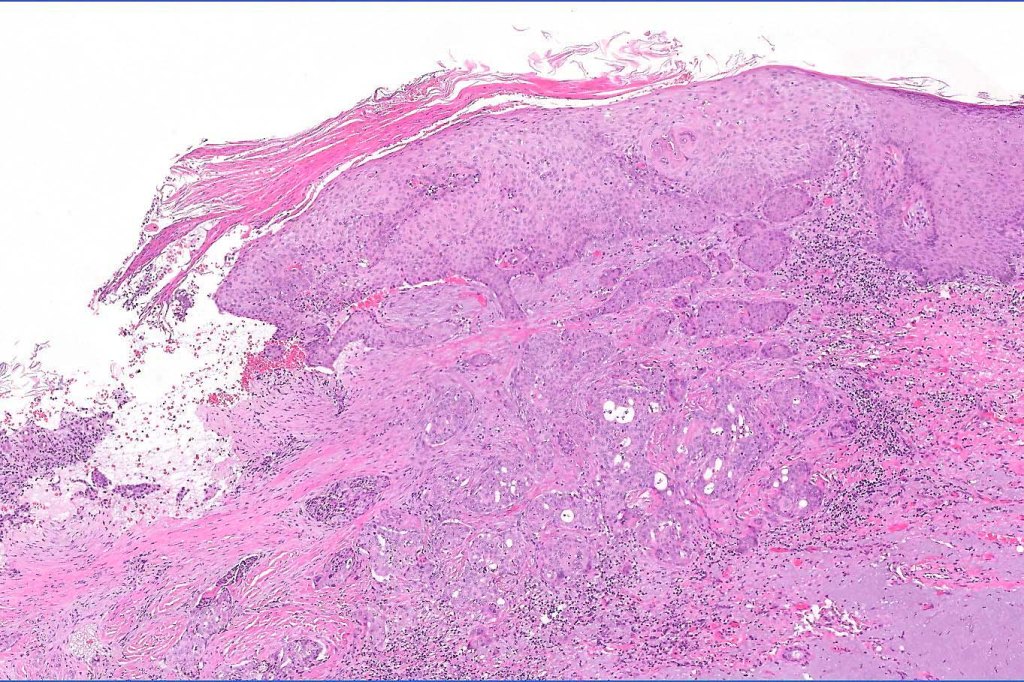

•Ulceration and solar elastosis are common

•Widely infiltrating biphasic tumor

•Superficial SCC

•Adenocarcinoma in deeper reaches

•Often extends to the subcutaneous fat